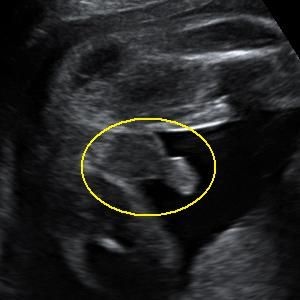

• A simple google search can answer your question. I pulled these from google:

Three lines = girl

Twig and berries = boy